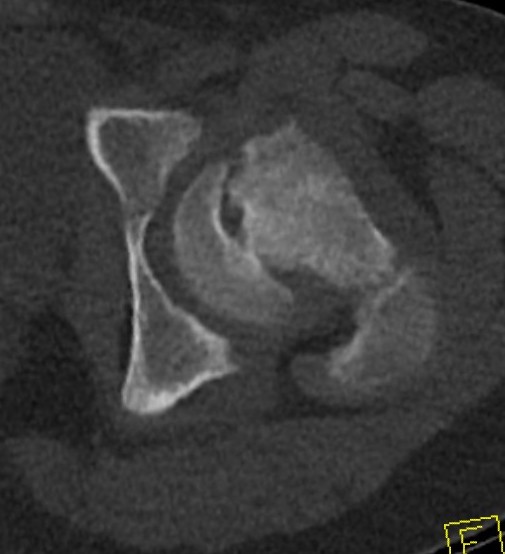

CT Scan